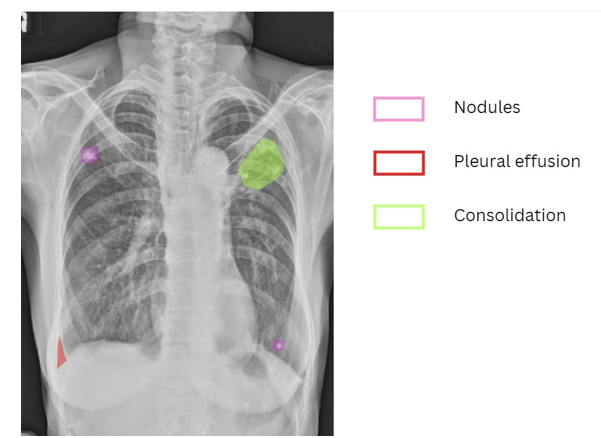

Acute TB represents a clinical emergency due to its rapid progression and severe manifestations, including persistent cough, high fever, and significant weight loss. Radiographic features such as consolidation, nodules, cavities, and costophrenic angle blunting are key indicators of active infection and inflammation observable on chest X-rays [5]. However, accurate identification of these pathologies is often hindered by overlapping anatomical structures, poor imaging quality, and the inherent subjectivity of manual interpretation.

The annotation phase focused on collecting and annotating chest X-ray images specifically for acute TB screening [11]. Chest X-rays were annotated for key pathologies associated with acute TB, including consolidation, nodules, cavities, and blunting of the costophrenic (CP) angle [12]. These features were meticulously labeled, capturing specific details such as size, location, and visual appearance to ensure precise representation of acute TB pathologies [13].

The performance of the model for acute TB screening was evaluated using precision, recall, Area Under the Curve (AUC), and Intersection over Union (IoU). High precision and recall values demonstrated the model’s accuracy in identifying critical acute TB pathologies such as consolidation, cavities, and nodules, ensuring reliable detection and localization.

The AUC metric provided a comprehensive measure of the model’s ability to distinguish between TB-positive and TB-negative cases, reflecting its diagnostic reliability. Additionally, the IoU metric assessed the accuracy of spatial localization by quantifying the overlap between predicted regions and ground truth annotations. Together, these metrics confirmed the model’s effectiveness in delivering precise and actionable diagnostic insights for acute TB.

The implementation of the Vision-Language Model (VLM) for acute TB screening has demonstrated significant potential to enhance diagnostic accuracy and efficiency, particularly in low-resource settings. The model achieved precision and recall rates above 97% for key acute TB pathologies, including consolidation, cavities, and nodules, underscoring its reliability for detecting critical indicators of the disease. By leveraging transformer-based encoders and the Gemma-3b decoder, the model effectively integrates visual and textual data to deliver context-aware diagnostic insights, reducing the reliance on radiologists in underserved areas.

The architecture’s strength lies in its cross-modal attention mechanisms, which align visual features from chest X-rays with clinical context, improving diagnostic accuracy. AUC values exceeding 0.97 for nodules, consolidation, and cavities highlight the model’s robustness in distinguishing between TB-positive and TB-negative cases. Additionally, high Intersection over Union (IoU) scores for pathologies like consolidation and cavities demonstrate the model’s ability to accurately localize pathological features, essential for effective treatment planning.